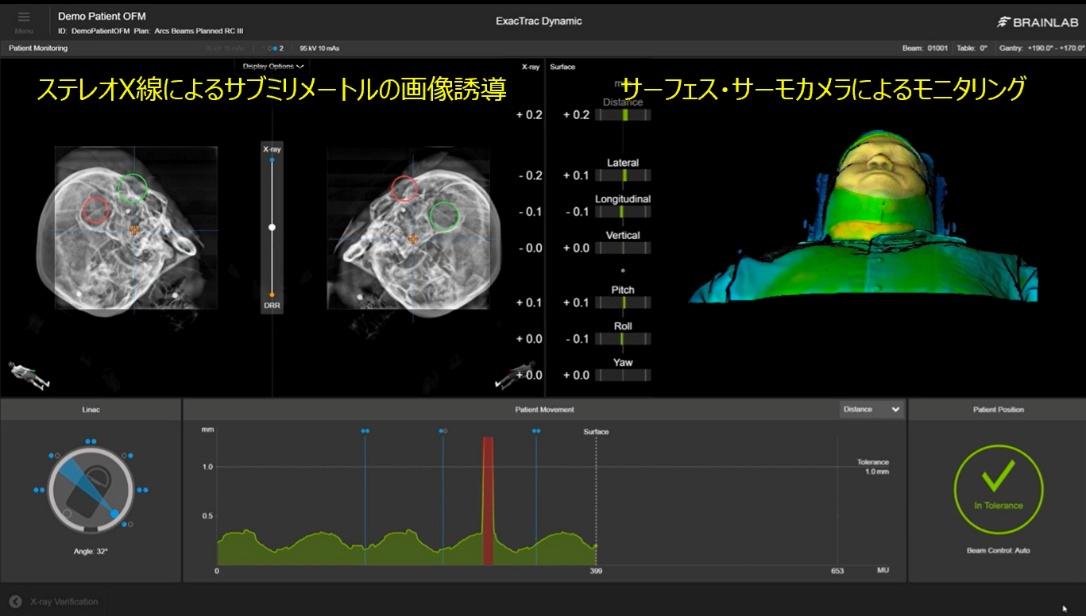

ステレオX線画像誘導システム(ExacTrac Dynamic)

ExacTrac Dynamic は、2台のX線装置により骨構造などの内部解剖情報を撮影し、治療計画画像と高速に照合することで、サブミリメートルレベルの高精度な患者位置合わせを可能にします。特に、高精度な脳定位放射線治療(SRS/SRT)の実施において有効です。

また、光学技術とサーモグラフィを用いた熱監視システムにより、患者さんの体表面を三次元的に認識し、治療中の体動をリアルタイムで監視します。患者さんの位置が設定された許容範囲から外れた場合には、自動的に照射を停止し、再位置合わせを行うことが可能です。